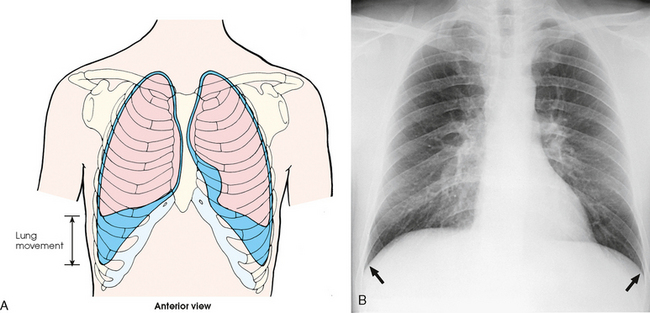

Each lung is divided into lobes by deep fissures. The fissures lie in an oblique plane inferiorly and anteriorly from above, so that the lobes overlap each other in the AP direction. The oblique fissures divide the lungs into superior and inferior lobes. The superior lobes lie above and are anterior to the inferior lobes. The right superior lobe is divided further by a horizontal fissure, creating a right middle lobe (see Fig. 10-4). The left lung has no horizontal fissure and no middle lobe. The portion of the left lobe that corresponds in position to the right middle lobe is called the lingula. The lingula is a tongue-shaped process on the anteromedial border of the left lung. It fills the space between the chest wall and the heart.

Fig. 10-4 A, Three views of the lung. B, CT axial image through the thorax. Right and left lungs are shown in actual position within thorax and in relation to heart. Note nodule in right anterior lung (arrow). (B, Courtesy Siemens Medical Systems, Iselin, NJ.)